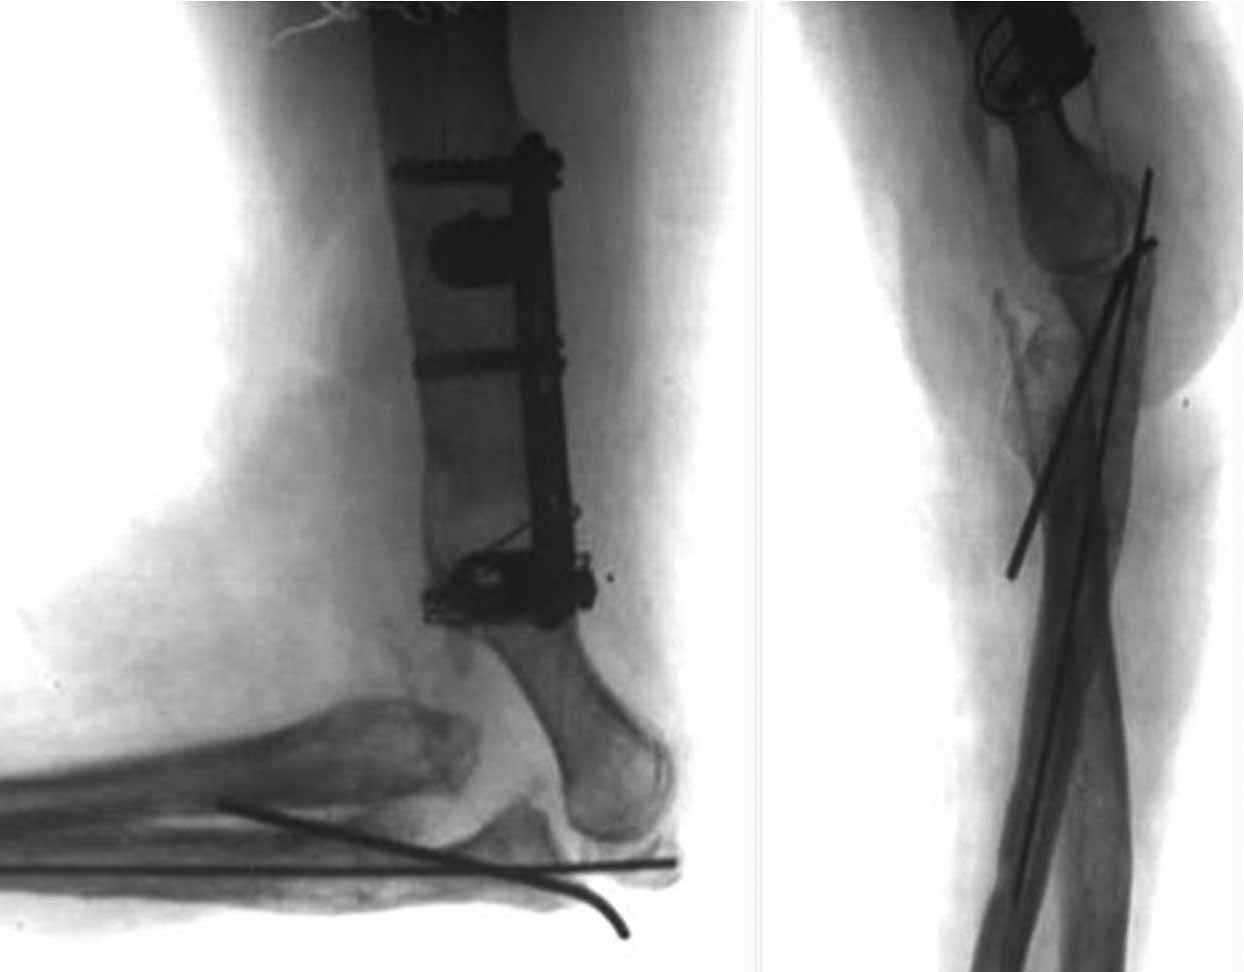

Как возможный вариант лечения, если от суставных поверхностей локтевого сустава ничего не осталось- это свободная пересадка васкуляризированного 1-го плюсне-фалангового сустава на сосудистой ножке из тыльной артерии в позицию локтевого сустава.

Имя     : Рисунок3.jpg